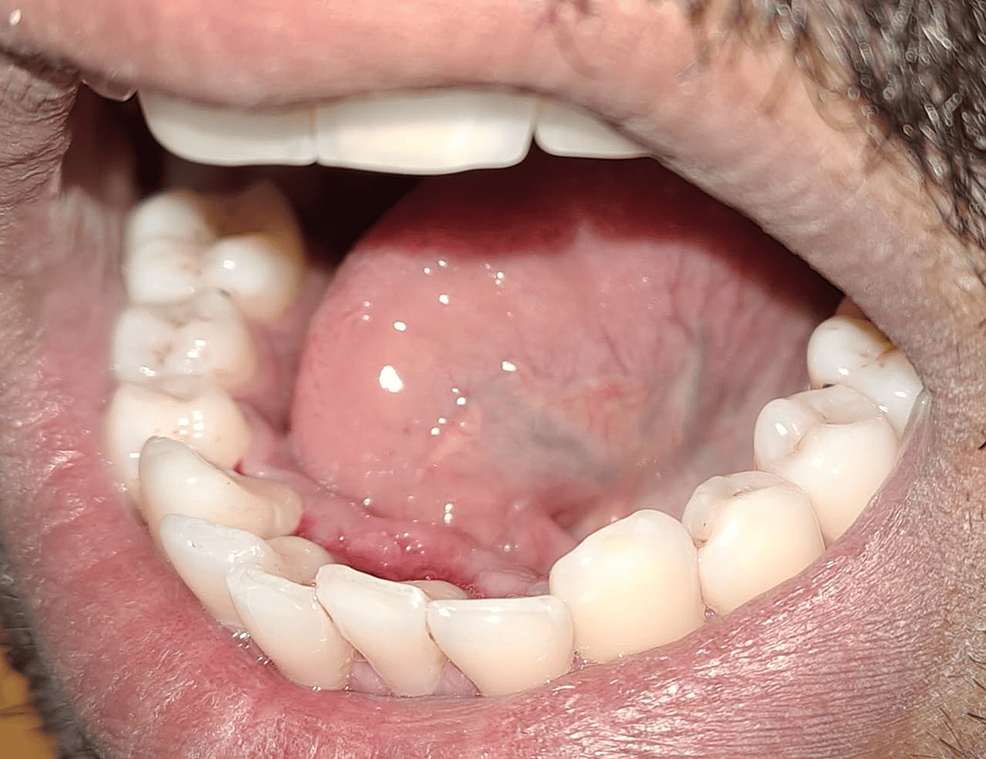

Immediately after frenectomy using 810 nm diode laser. There is no Diode Laser For Frenectomy A diode laser was used to treat a variety of oral. After obtaining informed consent from the patient, lingual frenectomy was envisaged by utilizing soft tissue diode laser. Like the co2 laser, the diode laser can be used for soft tissue surgery without extensive experience in the field of oral surgical. The qct also understands that frenectomies done with laser. Diode Laser For Frenectomy.

Immediately after frenectomy using 810 nm diode laser. There is no Diode Laser For Frenectomy Like the co2 laser, the diode laser can be used for soft tissue surgery without extensive experience in the field of oral surgical. Diode laser frenectomy is a safe and effective approach for treating. After obtaining informed consent from the patient, lingual frenectomy was envisaged by utilizing soft tissue diode laser. A diode laser was used to treat a variety. Diode Laser For Frenectomy.